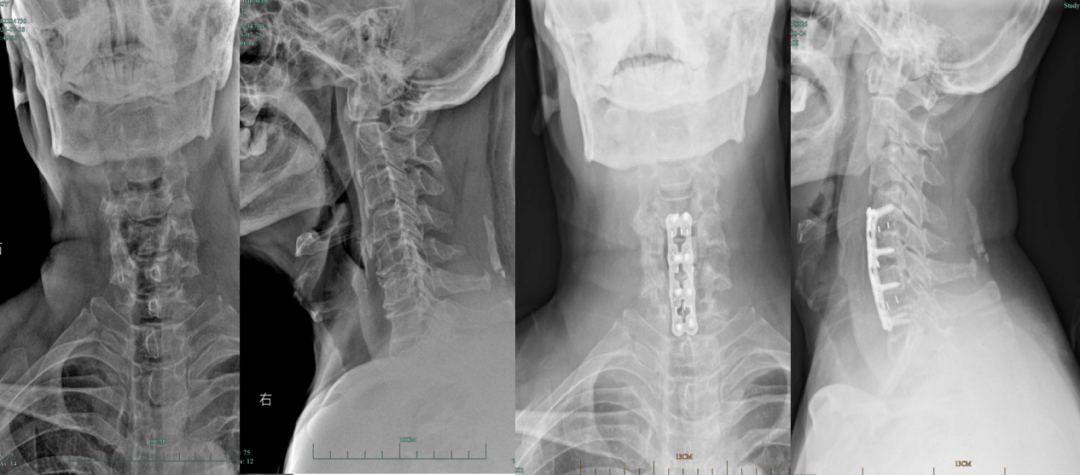

病例分享

术前术后X线:

术后CT:

术前术后MRI: